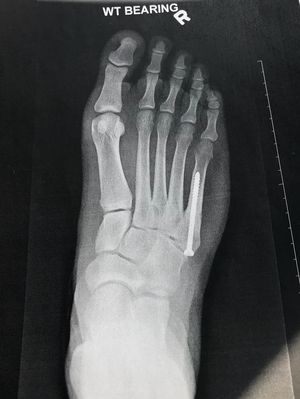

5th metatarsal repair surgery, 4 months post op

A follow up to a previously posted surgery, which can be seen, along with other X-ray angles on my profile